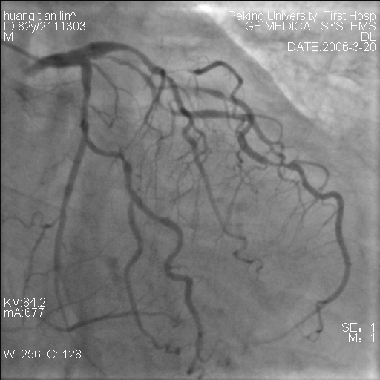

远端保护装置在急性心肌梗死中的应用(图)

远端保护装置在急性

心肌梗死

中的应用